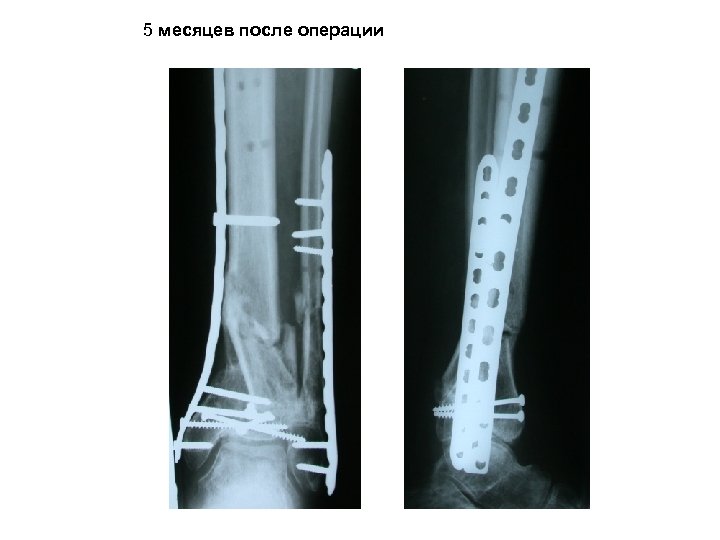

7 сутки после травмы. После спадения посттравматического отека мягких тканей Малоинвазивный (через минимальные разрезы) остеосинтез костей голени пластинами

5 месяцев после операции